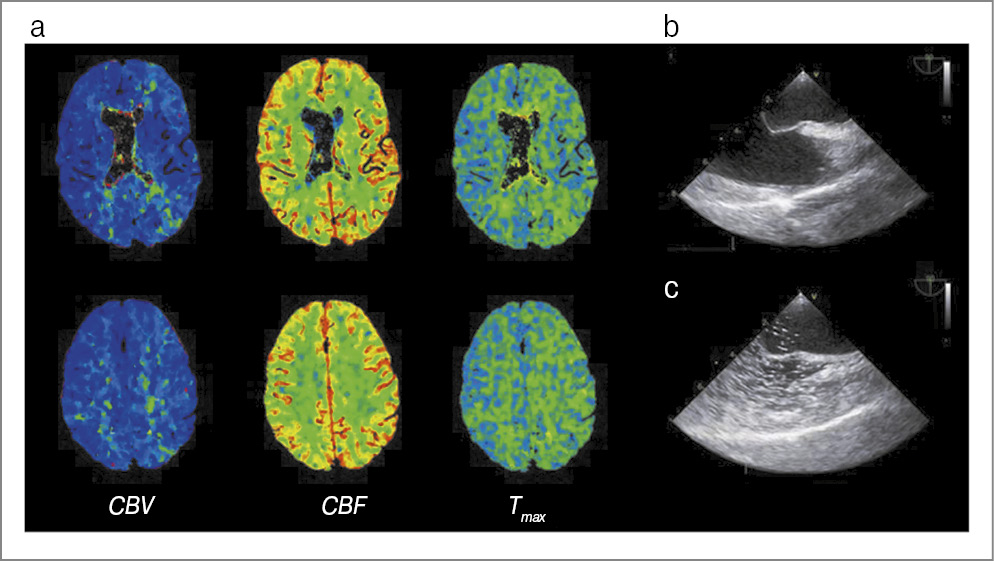

При поступлении наблюдались умеренная сенсомоторная афазия и правосторонняя гемианопсия. Проведена КТ ГМ, зон патологической плотности не выявлено. Признаков окклюзии крупных и средних артерий, а также венозного тромбоза по данным КТ-ангиографии не обнаружено. По данным КТ-перфузии отмечалось замедление кровотока (удлинение показателя Tmax) в левом полушарии ГМ – в зонах, выходящих за границы артериальных бассейнов. Выполнена МРТ ГМ: зафиксировано локальное повышение интенсивности на изотропной карте (b-1000) с понижением МР-сигнала на ИКД-картах от коры левой лобной доли, что соответствовало цитотоксическому отеку; изменений на FLAIR при этом не наблюдалось (рис. 3). Учитывая диагностические сомнения, принято решение провести внутривенный тромболизис. Примерно в 17:00 все симптомы регрессировали. Контрольная КТ ГМ не выявила патологических изменений. В рамках выяснения причины пролонгирования МА выполнена чреспищеводная ЭхоКГ: выявлена аневризма межпредсердной перегородки (R-тип, глубина 10 мм) в сочетании с ООО диаметром 2 мм (рис. 3, d). При тугом наполнении правых камер аэрированным физиологическим раствором во время натуживания отмечался массивный сброс микропузырьков в левое предсердие (рис. 3, e). По данным дуплексного сканирования тромбов в венах нижних конечностей не обнаружено. На 5-е сутки заболевания выполнена контрольная МРТ ГМ, результат которой оказался нормальным. Пациентка выписана в удовлетворительном состоянии.

Рис. 3. Клинический случай №3: a – КТ-перфузия; b – ДВИ; c – ИКД-карты МРТ; d, e – чреспищеводная ЭхоКГ (описание в тексте).

Третий клинический случай примечателен тем, что пролонгирование ауры сопровождалось транзиторным цитотоксическим отеком коры ГМ. Ранее аналогичные, но более выраженные изменения описаны при гемиплегической мигрени [29, 30]. Схожий с нашим клинический случай транзиторного изменения МР-сигнала на ДВИ описан в 2010 г. R. Belvís и соавт. у пациентки с персистирующей зрительной аурой [31]. Кроме того, обсуждаемый случай интересен тем, что дежурным неврологом принято решение провести внутривенный тромболизис. Это обусловлено трактовкой повышения МР-сигнала на ДВИ ишемическим процессом, что представляется совершенно оправданным в экстренной ситуации. Важно отметить, что при невозможности надежно дифференцировать инсульт и его маску целесообразно выполнить внутривенный тромболизис в силу его относительной безопасности – риск симптомного кровоизлияния в этой ситуации не превышает 0,4% [32].

Важно отметить, что у второго и третьего пациентов выявлено открытое овальное окно (ООО) с массивным право-левым шунтом. Взаимосвязь мигрени и ООО представляется интригующей: окно может служить источником микроэмболии или порталом для нее (из венозного русла), что приводит к развитию ишемически-индуцированной корковой распространяющейся деполяризации; наличие ООО препятствует метаболизму вазоактивных метаболитов в легких, а также связано с синдромом обратимой церебральной вазоконстрикции [33, 34]. На наш взгляд, данные ассоциации могут быть особенно актуальны для мигрени с пролонгированной аурой. Однако практическая значимость аномалии у пациентов с мигренью противоречива: окклюзия ООО или/и применение антитромботических препаратов не входят в рутинную клиническую практику, хотя могут быть показаны в отдельных случаях (мигрень с резистентной аурой, гиперинтенсивность белого вещества) [35–37].